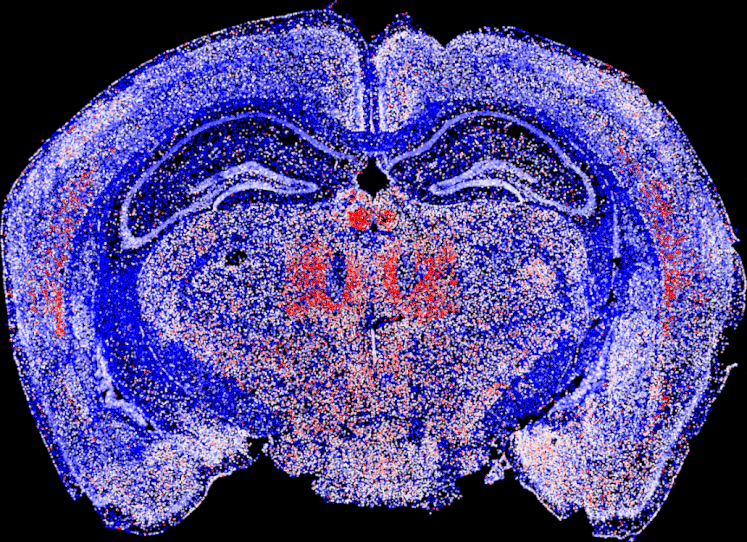

Cell Type Annotation

Transcriptional Program Scores